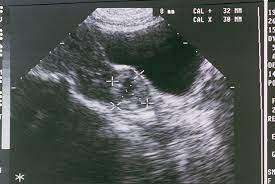

Ectopic pregnancy test progression. So its kind of hard to use that as a reference. If your doctor thinks you are having an ectopic pregnancy they will usually perform an ultrasound sonogram. This is called a tubal pregnancy.

We sadly lost our little one to an ectopic pregn. This is called a tubal pregnancy. The discharge or bleeding colour of an ectopic pregnancy is usually light pink or dark brown. In the case of an ectopic pregnancy the fertilized egg doesnt attach to the uterus. In more than 90 of cases the egg implants in a fallopian tube. This condition can lead to bleeding in the mother. To make sure that your levels are raising.